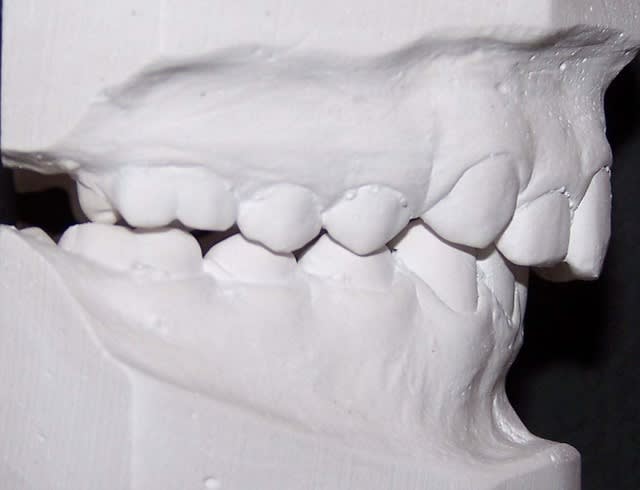

cas 2;Lea

BHG 9mois PUIS eln +2 LBs 15mois

l'occlusion;

NB: Dans les 2 cas , pas de version des inc infs!